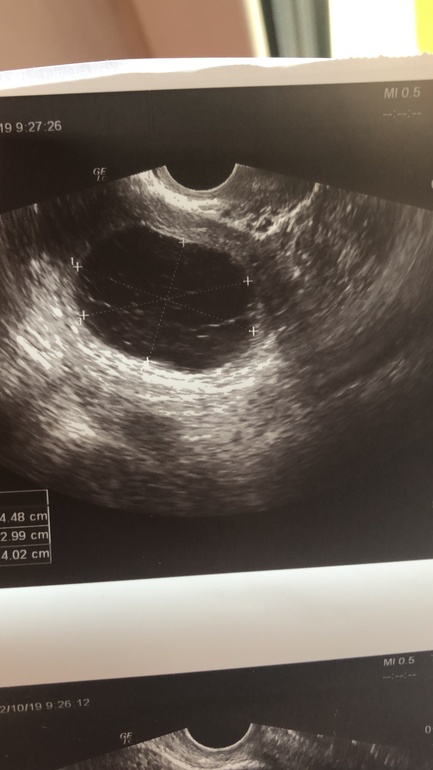

Сегодня пришла на узи (22дц)

Эндометрий-12,5

И киста в ЛЯ (в нем был ДФ)-ставят под вопросом КЖТ или эндометриойдная .

Но потом логически подумала ,что 18 я была на узи и все было хорошо,а 22 уже киста 4см...вряд ли она за 3 дня может до таких размеров вырасти.

Так что я склоняюсь к КЖТ.

Ну кто же Вам тут ответит на этот вопрос? Эти две кисты даже опытный УЗИст не отлечит. У них одна эхогенность. Единственная возможность их отличить это: если она уйдет иди уменьшается, то это фолмкулярная киста или ЖТ. А если на протяжении нескольких циклов она в прежних размерах или выросла то это эндометриойдная.